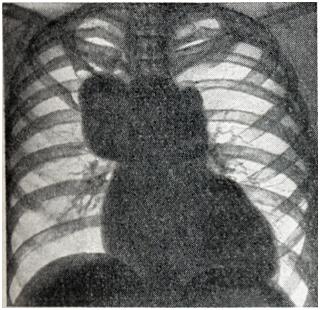

Рис. 5.

Аневризма восходящей и грудной аорты. Атрофия I и II ребер справа в переднем отделе (рентгенограмма).

Дифференциальный диагноз аневризмы аорты с опухолями и кистами средостения представляет большие трудности. Признак пульсации имеет лишь ограниченное значение: она может быть передаточной при опухолях и отсутствовать при тромбированной аневризме или сращениях. Рекомендуется применение томографии и пневмомедиастинографии. Кроме обычно встречающихся вторичных признаков — смещения пищевода и трахеи, возможна картина ателектаза легкого вследствие сдавления бронха, высокое положение диафрагмы из-за давления на диафрагмальный нерв, обеднение кровотока в легком ввиду сдавления легочного ствола, атрофия от давления тел позвонков, ребер (рис. 5). Рентгенологическое распознавание аневризмы брюшной аорты по обычным снимкам возможно лишь при наличии обызвествления стенок аорты или типичной деструкции тел позвонков. В предоперационном диагнозе всех аневризм аорты решающее значение имеет аортография.